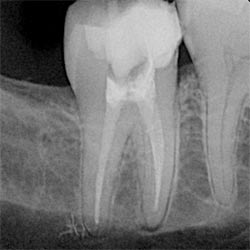

An X-ray image of a lower molar tooth with a white filling visible in each root.a root-filled molar

The image above shows a root canal filling in a molar tooth.